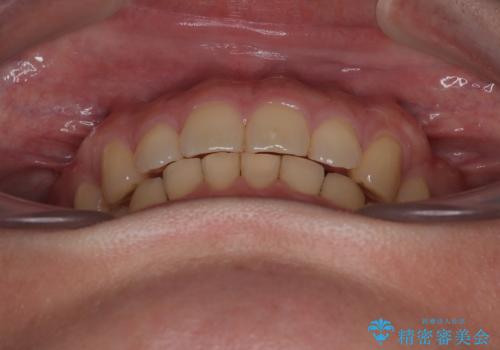

- 下顎前歯が完全に隠れてしまっていることを気にして来院された患者様です。

下顎の臼歯が手前に傾斜していることで咬み合わせが深くなってしまい、下顎前歯が見えないほどに上顎前歯が覆い被さっている状態でした。